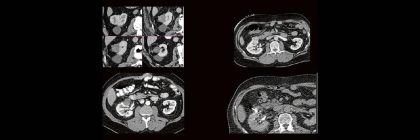

Professor Dr. med. Marc Brockmann WEITERENTWICKLUNGEN VON KOPF BIS FUSS BEIM VC Oberstarzt Dr. med. Stephan Waldeck DEEP-LEARNING-REKONSTRUKTION IN DER NEURORADIOLOGIE Die CT ist ein essentielles Routine-Verfahren in der Neuroradiologie. Weiterlesen …